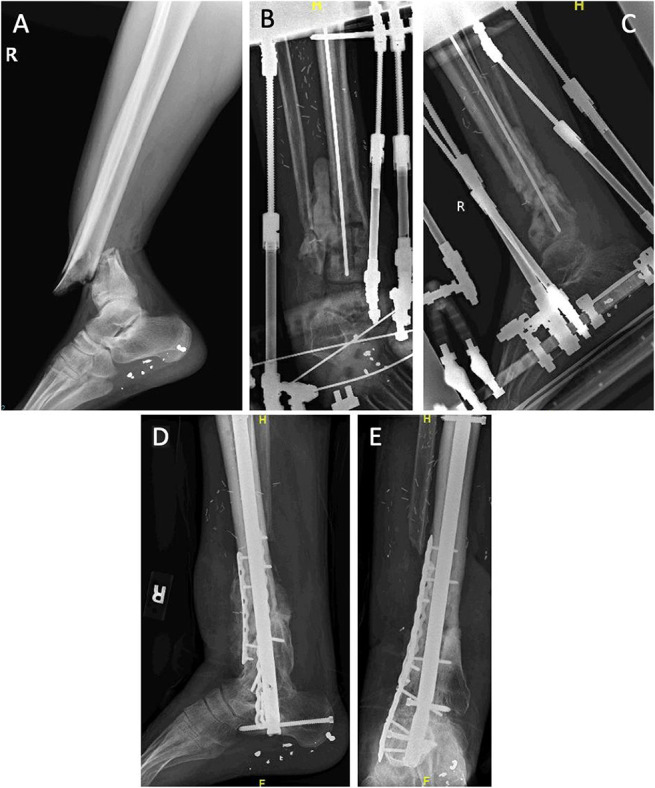

开放性骨折后出现严重骨质流失的情况虽然相对少见,但多发生在高能量损伤中。在骨质严重流失的开放性骨折中,胫骨骨折占大多数。治疗胫骨骨质流失有多种不同的手术策略,各有利弊。外科医生在选择策略前应仔细研究适当的适应症和所有相关证据。

Critical bone loss after open fractures, while relatively uncommon, occurs most frequently in high-energy injuries. Fractures of the tibia account for the majority of open fractures with significant bone loss. A number of different surgical strategies exist for treatment of tibial bone loss, all with different advantages and disadvantages. Care should be taken by the surgeon to review appropriate indications and all relevant evidence before selecting a strategy.